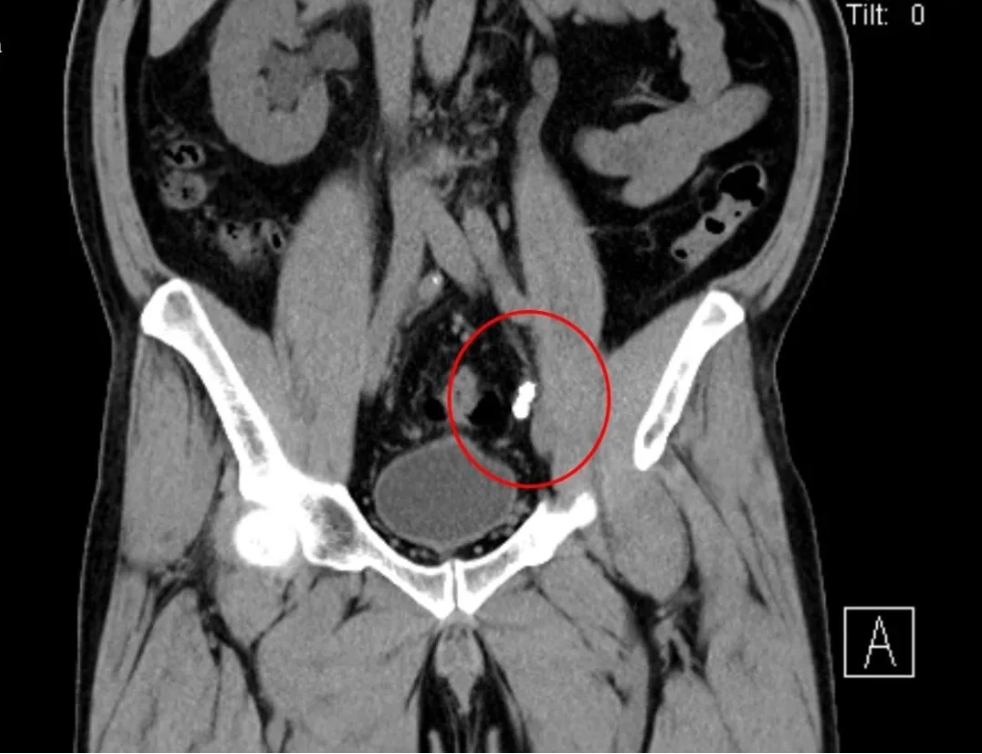

近日,我院成功为一名因双侧输尿管结石完全梗阻,导致急性肾功能衰竭的患者实施“双侧输尿管镜同期手术”,将患者肾功能从崩溃边缘拉回。经过精心治疗,患者肾功能已恢复正常,目前状态良好。60岁的谢先生,因突发右侧腰部绞痛到我院泌尿外科门诊就诊。经检查发现,谢先生双侧输尿管中段结石完全梗阻,这是典型的"石头堵死生命通道"!双肾出现重度积水,已达"红色警戒线"。肾盂扩张超3cm且皮质变薄。同时已发展为急性肾功能衰竭,肌酐值超过526μmol/L(男性正常值:54—106 μmol/L),尿素达18.1mmol/L(成人正常值:2.5—7.1 mmol/L)。

面对复杂的病情,我院泌尿外科副主任雷鸣迅速组织多学科会诊,经过详细讨论,科室团队一直认为,患者双侧输尿管结石和双肾积水是导致急性肾功能衰竭的主要原因,必须尽快手术解除梗阻,恢复肾脏功能。考虑到谢先生的肌酐值太高,为了稳定其内环境,先进行血液透析,再实施手术解除梗阻更妥。经过血液透析,使肌酐值降至300μmol/L,为后续手术争取了宝贵时间。为避免二次创伤,泌尿外科决定采用“双侧输尿管镜同期手术”方案,一次解决双侧梗阻。术前,通过CT三维重建技术精准定位结石位置,并根据透析后患者身体状况评估手术耐受性。术中,雷鸣带领泌尿外科团队为谢先生实施了经尿道输尿管软镜右侧输尿管激光碎石取石+经尿道输尿管硬镜左侧输尿管激光碎石取石术。运用双镜联合技术,超细输尿管硬镜与软镜协同操作,硬镜快速疏通近端梗阻,软镜处理肾盂残留结石;使用钬激光将双侧结石逐层粉末化,并通过负压吸出碎屑,有效避免术后“石街”形成;术后留置双侧双J管,保障输尿管通畅,促进肾功能恢复。